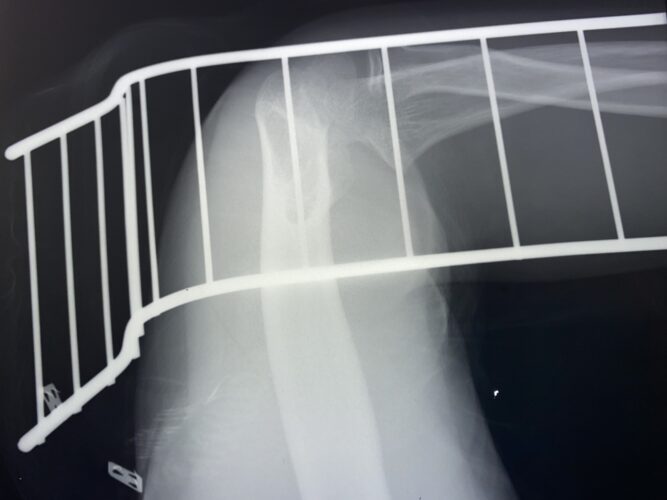

さわやか千葉県民プラザ(上腕骨外科頸骨折)

さわやか千葉県民プラザ(上腕骨外科系骨折)